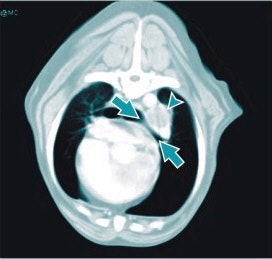

![]() |

| Libby the Rottweiler had an undifferentiated sarcoma of the left foreleg that recurred after excision. A CT of the thorax revealed an enlarged tracheobronchial lymph node (arrowhead), which caused compression of the left mainstem bronchus (arrows). Image courtesy of Animal Imaging of Los Angeles. |